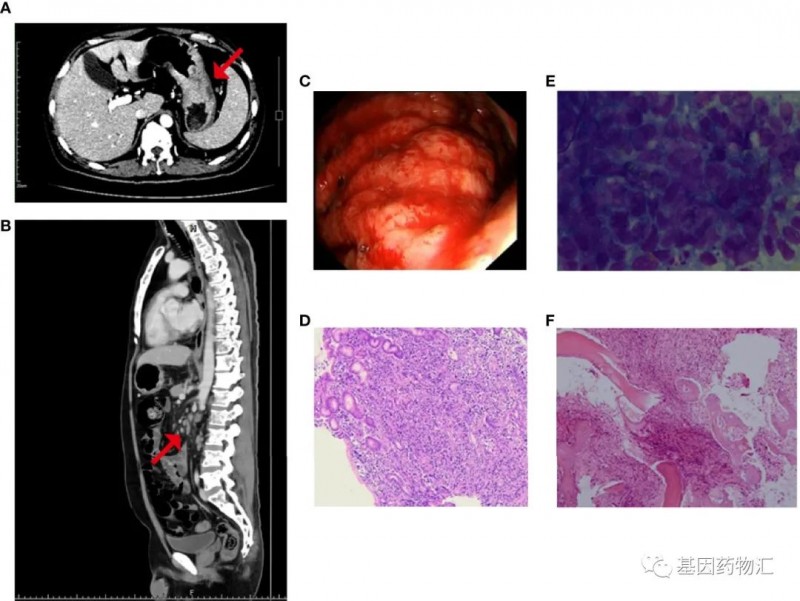

一位男性患者,51岁,2014年10月确诊腹部及后腹膜淋巴结转移性腺癌,基于免疫组化检查结果,原发部位首先考虑消化系统来源,胃系统来源可能性最大。

考虑到患者年龄较小,身体状况良好,肿瘤负荷较大,且较大可能性为转移性胃癌,因此选择了三药联合曲妥珠单抗的方案,即奥沙利铂+多西他赛+卡培他滨化疗方案与曲妥珠单抗靶向治疗联合。

患者首先完成了6个周期的治疗,腹部及腹膜后转移淋巴结明显减少。随后的治疗中,患者病情稳定无进展。

至2015年6月,患者复查时发现后腹部淋巴结明显增多,因此改用奥沙利铂+S-1(爱斯万)化疗方案联合曲妥珠单抗靶向治疗。治疗2个周期,患者耐受性较好,局部有复发,给予同步放化疗(胃微弯及腹膜后淋巴结放疗,与卡培他滨合用)。

但非常不幸的是,2015年12月患者复查CT时发现,肝右叶疑似出现了转移病灶。经过医生与患者家属的探讨,决定尝试阿帕替尼方案。

患者于2015年12月~2016年1月期间使用阿帕替尼靶向治疗,但治疗并没有效果。上腹部核磁共振检测结果显示,肝转移癌,共16个病灶,体积增大,且胃贲门旁淋巴结肿大。

为了更好地指导下一步的用药方案,患者接受了二代测序(NGS)。检测结果显示,患者MET基因扩增约4.1倍,ERCC基因扩增约2.2倍。随后,患者开始接受克唑替尼治疗。

当年,几款c-MET抑制剂都还没有上市,临床上能够应用于MET异常患者的只有几款多靶点的药物,其中就包括了当时已经获批应用于晚期ALK阳性非小细胞肺癌的ALK/ROS1/MET多靶点抑制剂克唑替尼。

用药2个月后,复查上腹部MR结果显示:患者肝脏未见明显转移瘤,胃贲门旁淋巴结较之前略微缩小,提示肝转移病灶完全缓解!

最终,患者得到了长达20个月的无进展生存期。